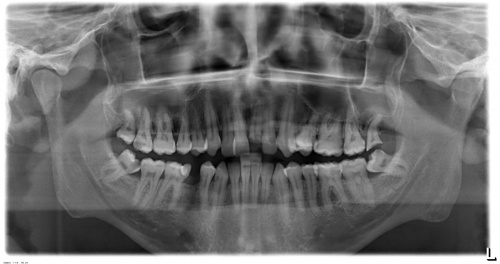

Czy odbudowa zęba jedynki jest możliwa?

Odbudowa złamanego zęba Witam Złamała mi sie jedynka która była w dość kiepskiej kondycji, zrobiłem zdjęcie RTG https://images82.fotosik.pl/942/8ce07c80f9eeac22med.jpg Będzie możliwość odbudowy tego zęba ? jaki może być tego koszt? Z góry dziekuje za odpowiedz

odpowiada 1 ekspert:

Lek. dent. Konrad Rutkowski